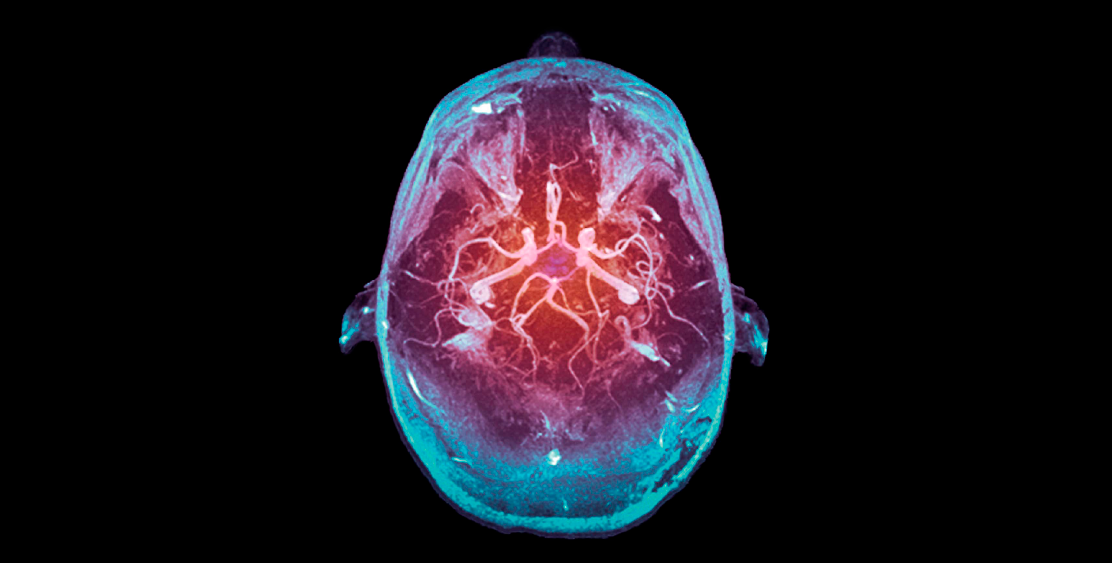

Las arterias vertebrales se fusionan intracranealmente formando un tronco conocido como arteria basilar. En la siguiente imagen puedes observar el énfasis en las regiones que irriga el sistema carotídeo y vertebrobasilar:

Corte transversal de cerebro humano, el circuito cerebral arterial y sus principales áreas de irrigación

Círculo arterial cerebral

Círculo arterial cerebral Wikipedia. (s. f.). [Entrada: Circuito arterial cerebral] [gráfico]. Tomada de https://es.wikipedia.org/wiki/C%C3%ADrculo_arterial_cerebral